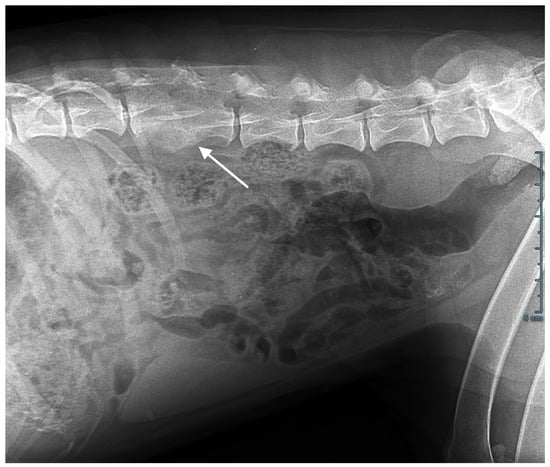

Abdominal ultrasonography, computed tomography, and an MRI scan showed T3-T4 thoracic and L2-L3 lumbar discospondylitis with osteolysis and non-compressive ankylosing hyperostosis (Figure 2); generalized lymphadenomegaly with a five-fold increase in lymph node volume and a loss of structure was also observed.

Figure 2. Abdominal X-ray. L2-L3 osteolysis and bone remodelling with fusion of the vertebral bodies (arrow).